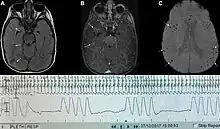

Graph showing Biot's respiration and other pathological breathing patterns.

Biot's breathing or ataxic breathing, is an abnormal pattern of breathing characterized by variable tidal volume, random apneas, and no regularity.[1] It is named for Camille Biot, who characterized it in 1876.[2][3]